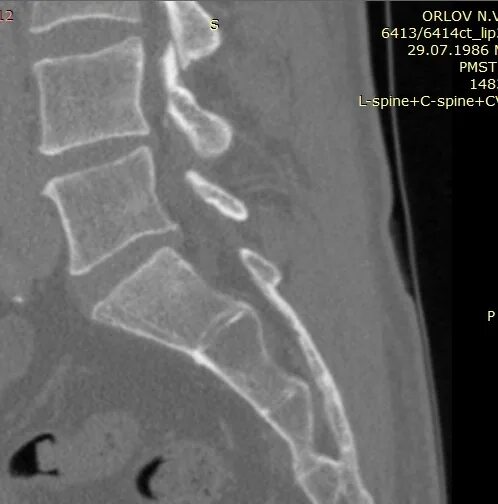

Сакроилеит на кт